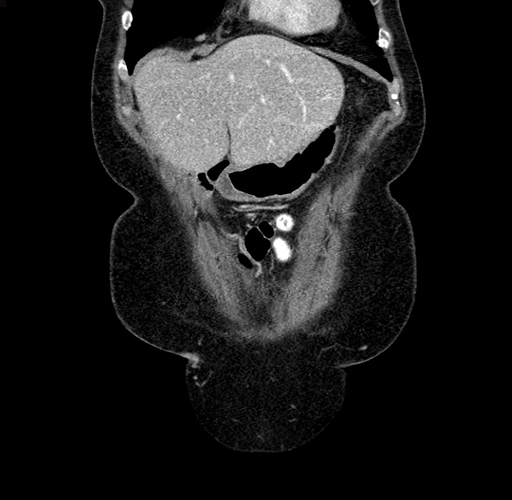

Pre-Chemo: Axial Venous